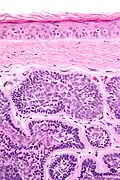

Micrograph of dermal cylindroma in H&E stain.

Micrograph of dermal cylindroma in H&E stain. -

Dermal cylindroma. Hyaline droplets visible in lobules.